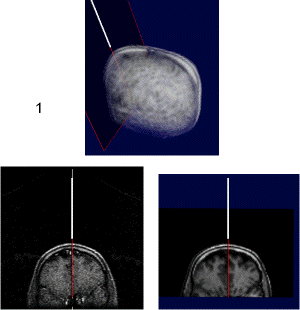

Interventional MR systems allow for a continuous monitoring of the brain typically in a plane through the tip of the intervention device. Whereas a microscope can see only the immediate neighbourhood, interventional MR can look ahead and to the sides which gives more information and security for planning the next step. As the quality and the number of slices generated by an interventional MR is worse than with the preoperative MR, there is a need for registrating and fusing the current slices of the interventional MR with the high quality reference scene.

upper: overview of scull with interventional device and associated scan plane; left: plane from interventional MRI scan (low quality); right: plane from preoperative MRI scan (high quality). Quicktime movie (180 KB) showing positioning of device. |

left: texture-based rendering of a 3D-CT-volume in real-time right: shadows added to improve depth perception Quicktime movie (610 KB) |